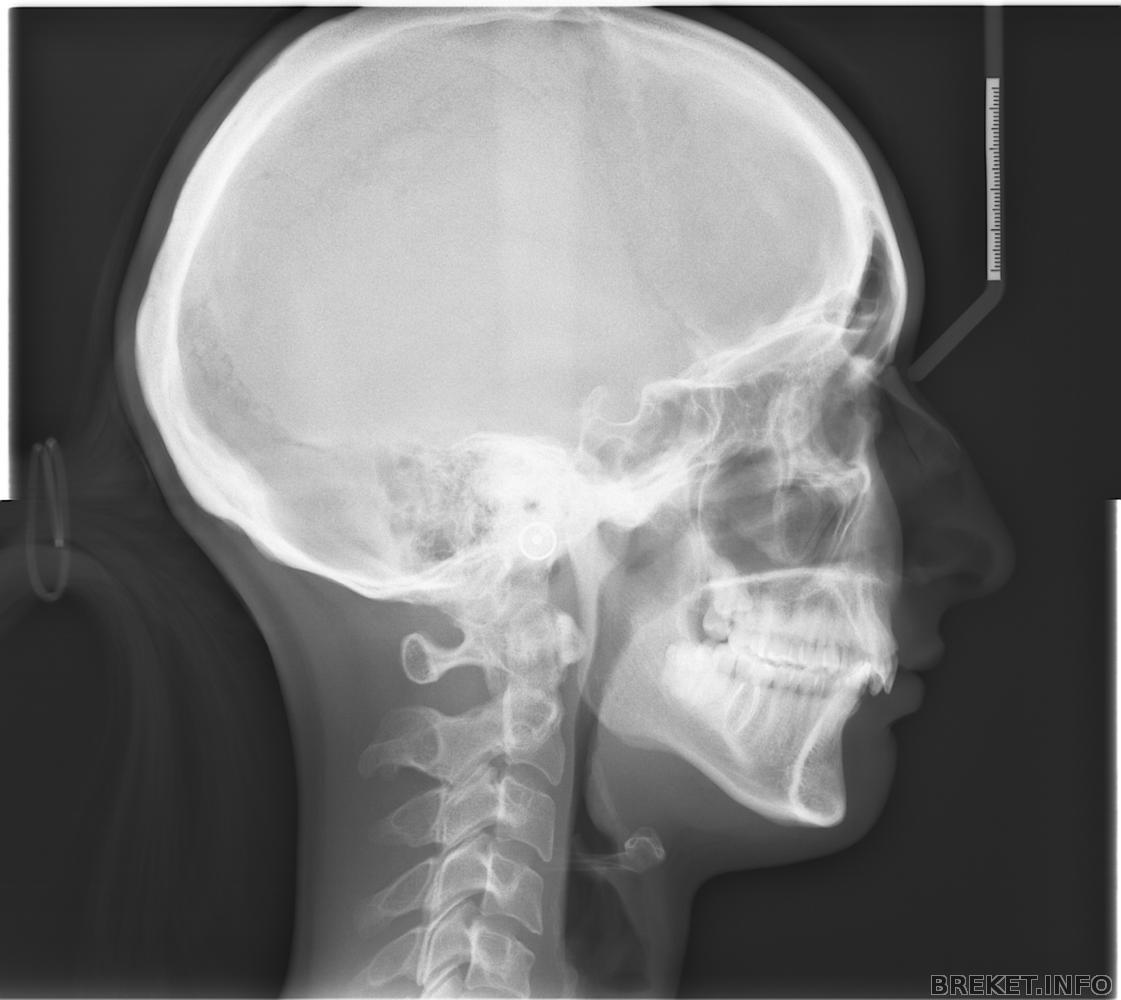

какой чудный хвостик на трг

И правда, мило получилось

честно говоря даже и не думала, что волосу будут видны на снимке))